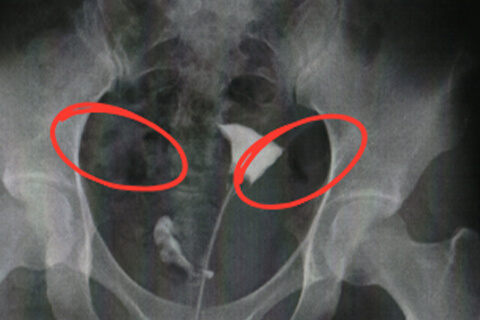

子宮卵管造影検査を行うことで卵管の閉塞や狭窄がないか調べることができます。検査は5分ほどで、痛みは通常はほとんどありません。卵管が狭窄している場合痛みを感じることがあります。麻酔は必要ありません。再診料・抗生剤等も合わせて約5,000円弱です。 子宮頚管から細いチューブを挿入し、その先端に付いたバルーンを膨らませて子宮内に固定します。造影剤を流しながらX線透視を行い、子宮の内部、卵管、腹腔まで造影剤が拡散していく様子を観察します。

片側閉塞

卵管は左右 1 本ずつありますが、片側だけが閉塞や狭窄を起こしている状態が片側狭窄、閉塞です。毎月の排卵が交互の卵管で起こるとは限らないこと、閉塞や狭窄がない卵管の状態が万全とは言えない場合もあることから、両側が正常な場合に比べると妊娠が成立する確率は低下します。

両側閉塞

卵管が左右とも閉塞や狭窄している状態です。両側閉塞では自然妊娠の可能性が限りなく低いため卵管鏡下卵管形成術が第一選択となります。